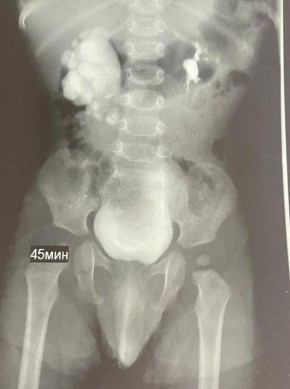

Патологию заметили ещё во время беременности мамы малыша, а сразу после его рождения специалисты взяли ребенка под наблюдение. Весной 2025 года обследование показало: у мальчика — гидронефроз. При этом заболевании почка...

У ребёнка ещё до рождения заметили проблемы с почкой на УЗИ, а после появления на свет состояние стало ухудшаться — диагностировали гидронефроз. При этом опасном состоянии почка могла бы перестать функционировать.В ноябре врачи ставропольской больницы...